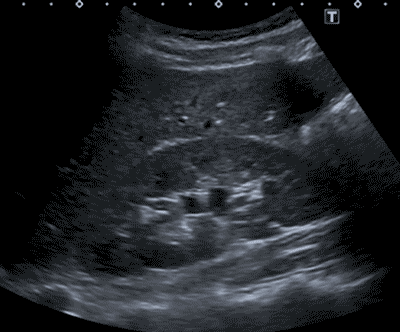

Echografie; normale nier